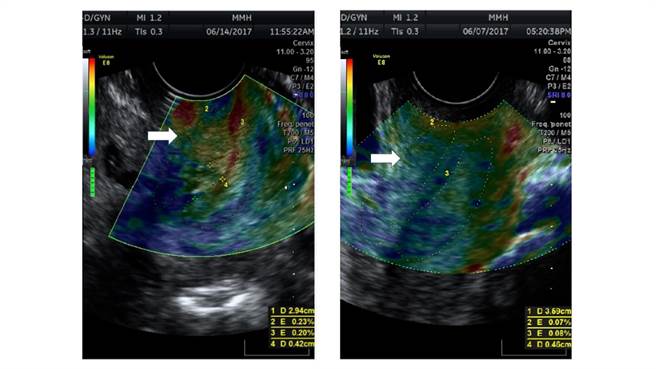

彩色超音波弹性成像技术,子宫颈闭锁不全的子宫颈在超音波下红色区域的比例增加(左),一般族群的子宫颈在超音波下大部分为蓝色区域(右)。(图/台北马偕医院提供)

近3年内马偕医院分析339位孕妇第1孕期子宫颈超音波弹性成像,发现其中的24名曾子宫颈闭锁不全,其子宫颈硬度明显较软;比起量测子宫颈长度,这样的方式更能早期预测子宫颈闭锁不全。